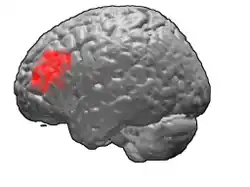

Brodmann area 46, or BA46, is part of the frontal cortex in the human brain. It is between BA10 and BA45.

BA46 is known as middle frontal area 46. In the human brain it occupies approximately the middle third of the middle frontal gyrus and the most rostral portion of the inferior frontal gyrus. Brodmann area 46 roughly corresponds with the dorsolateral prefrontal cortex (DLPFC), although the borders of area 46 are based on cytoarchitecture rather than function. The DLPFC also encompasses part of granular frontal area 9, directly adjacent on the dorsal surface of the cortex.

Cytoarchitecturally, BA46 is bounded dorsally by the granular frontal area 9, rostroventrally by the frontopolar area 10 and caudally by the triangular area 45 (Brodmann-1909). There is some discrepancy between the extent of BA8 (Brodmann-1905) and the same area as described by Walker (1940).[1]